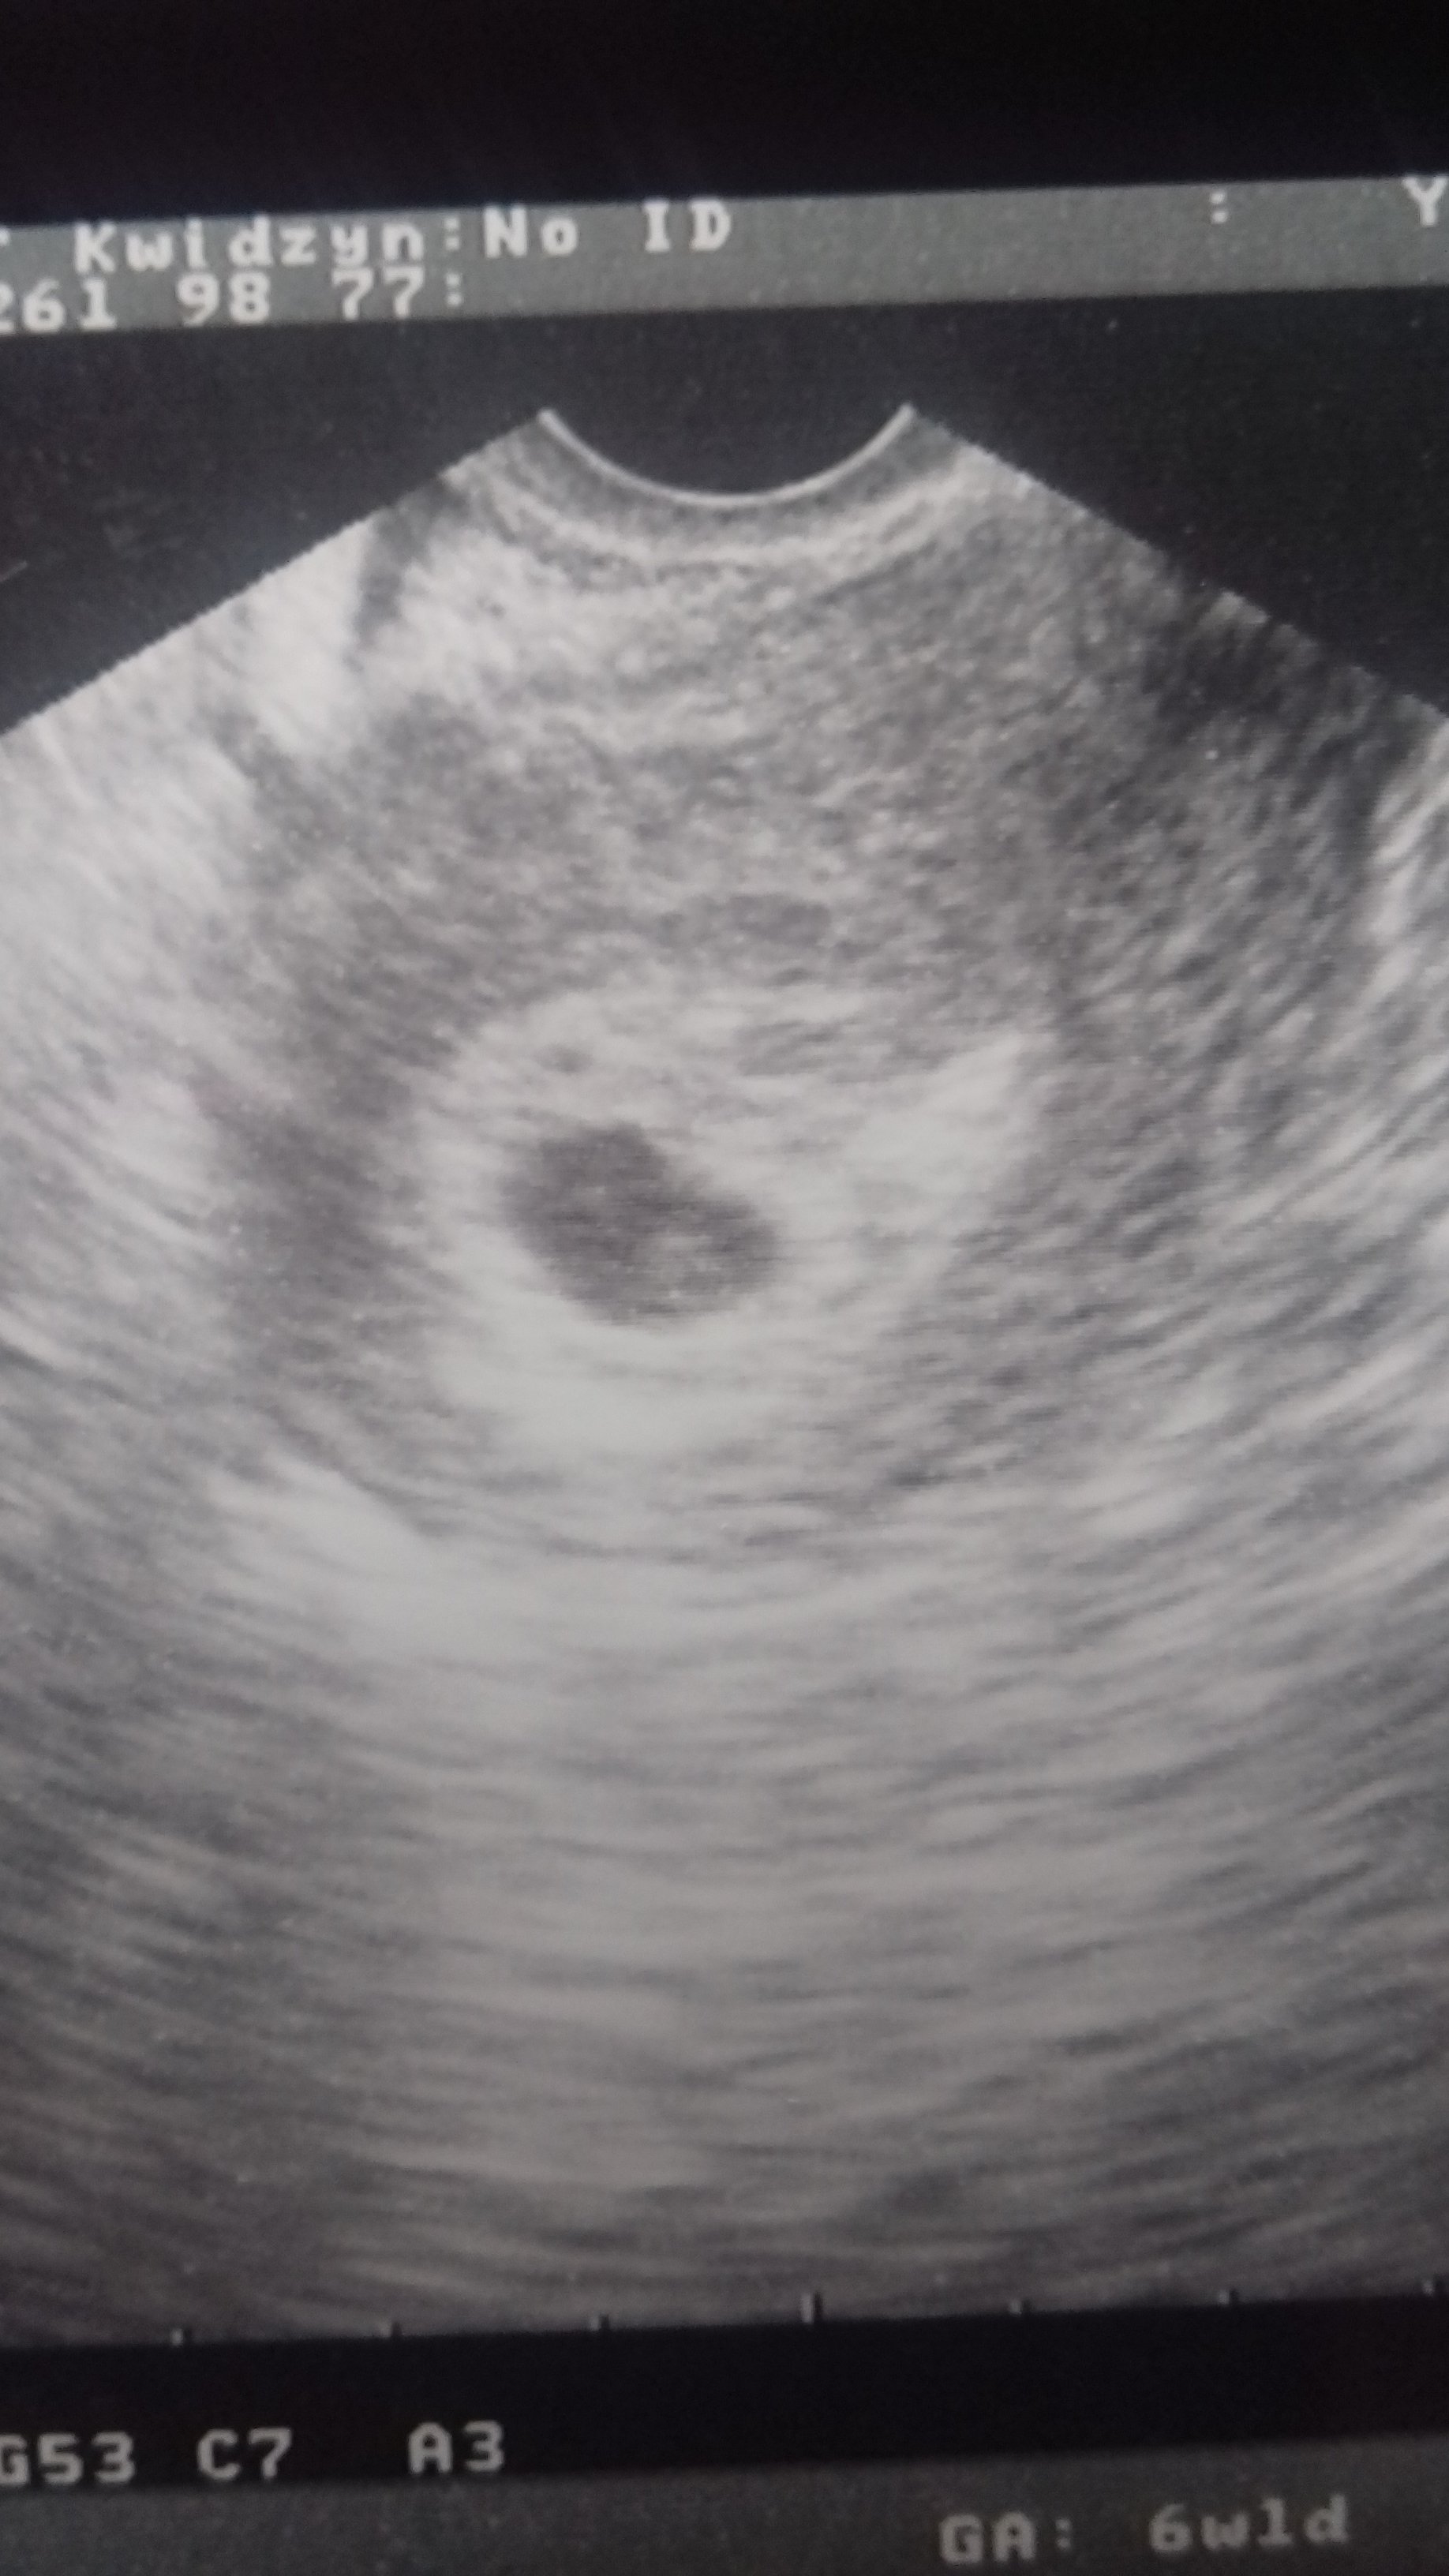

Kurcze u mnie akurat pecherzyka nie zmierzyl ;PU mnie w 6 tyg bylo serducho. Pecherzyk mial 15mm. Fasoli nie zmierzyla